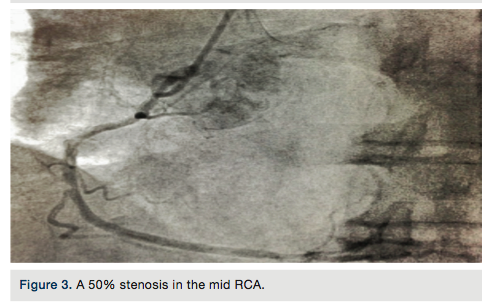

Following the catheterization, an echocardiogram was performed. The echocardiogram

confirmed a VSR with a left to right shunt (Figures 6a-b). The results from the echocardiogram were:

- Ejection fraction 35 to 40%;

- LV apical dyskinesis;

- Apical VSR;

- Left to right ventricular shunt.